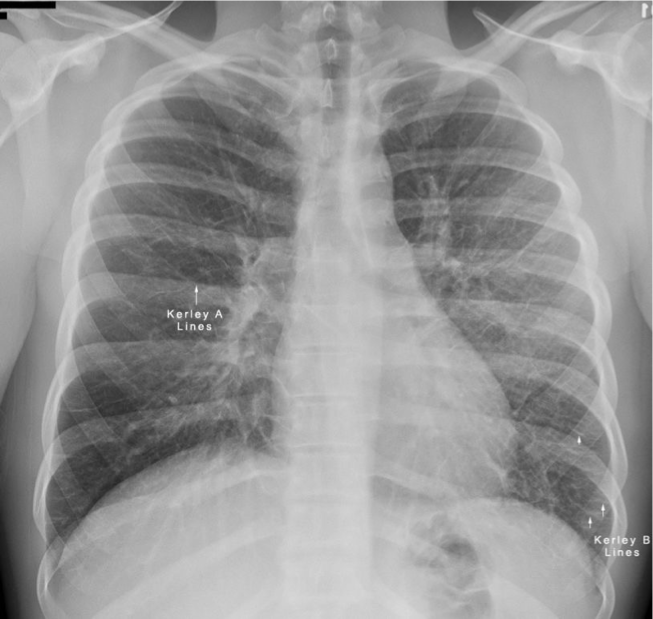

Differentiate between Kerley A vs Kerley B lines.

Kerley A: linear opacities extending from periphery to hila

Kerley B: small, horizontal, peripheral lines seen at the lung bases (represent thickened interlobular septa on CXR)

Interstitial infiltrate pattern on CXR found in patients with interstitial pulmonary edema?

Kerley lines